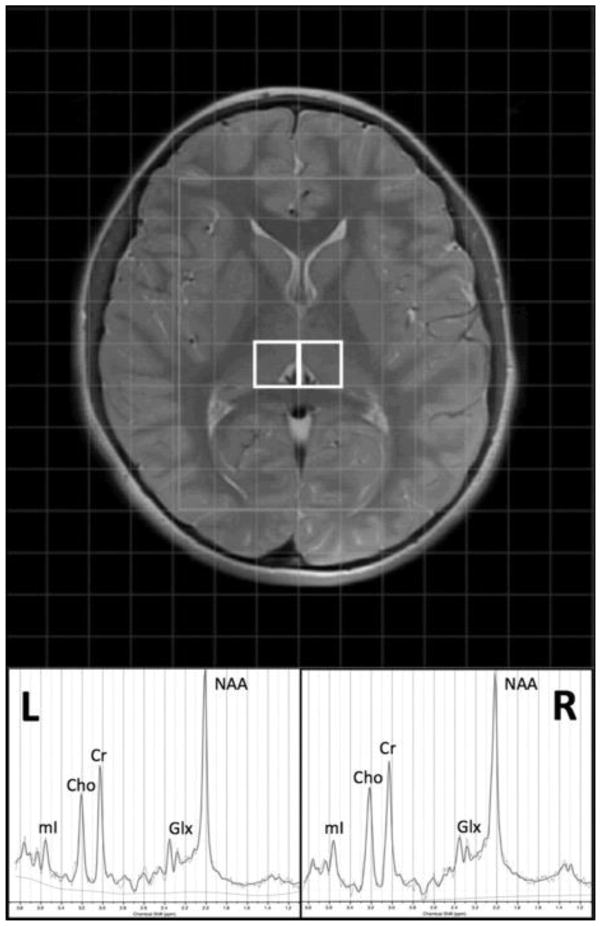

MRI processing was conducted utilizing SPM (Friston, 1994), LCModel (Provencher, 2001), and in-house Matlab scripts (The Mathworks Inc., Natick, Massachusetts, USA). Anatomical T2-weighted images were segmented with SPM8 to form partial volume maps of grey matter (GM), white matter (WM), and cerebrospinal fluid (CSF). The MRS grid was then co-registered to the anatomical images and partial volume maps utilizing in-house Matlab scripts. The anatomical volume corresponding to the midpoint of each MRS slab was used for registration of each voxel of interest (VOI). The grid was shifted within the acquisition plane to allow optimized localization based on anatomical structure. VOIs were centered on the right and left thalamus to include primarily thalamic GM (Figure 1) and had a nominal resolution of 1.5 × 1.5 × 2 cm. Additional VOIs centered on other deep brain structures relevant to the study of ASD, such as the head of the caudate/putamen, will be evaluated in future examinations of this multi-voxel dataset. Spectra were referenced to the standard PRESS basis set provided by LCModel and neurometabolites were quantified based on the ratio to creatine + phosphocreatine (tCr). The primary neurometabolite of interest was N-acetyl aspartate (NAA: a marker of neuronal integrity); however, choline-containing compounds including glycerophosphocholine + phosphocholine (Cho: a marker of cellular membrane degradation/maturation), myoinositol (mI: a glial cell marker), and glutamate + glutamine (Glx: the primary excitatory neurotransmitter and its major metabolite) were also examined on an exploratory basis. Initial quality assessment included visual inspection for standard peaks (NAA, Cho & tCr) and residual macromolecule and lipid signals. Cramer-Rao lower bounds (≤20 %) were used as a conservative threshold for the inclusion of individual neurometabolite data from each participant.

Figure 1. Thalamic voxel localization and representative 1H MRS spectrum.

Voxels in the left (L) and (R) thalamus and an example spectrum from LCModel (Provencher, 2001) are displayed with the primary neurometabolite peaks, including N-acetyl aspartate (NAA), choline-containing compounds including glycerophosphocholine + phosphocholine (Cho), creatine (Cr), myoinositol (mI), and glutamate + glutamine (Glx).